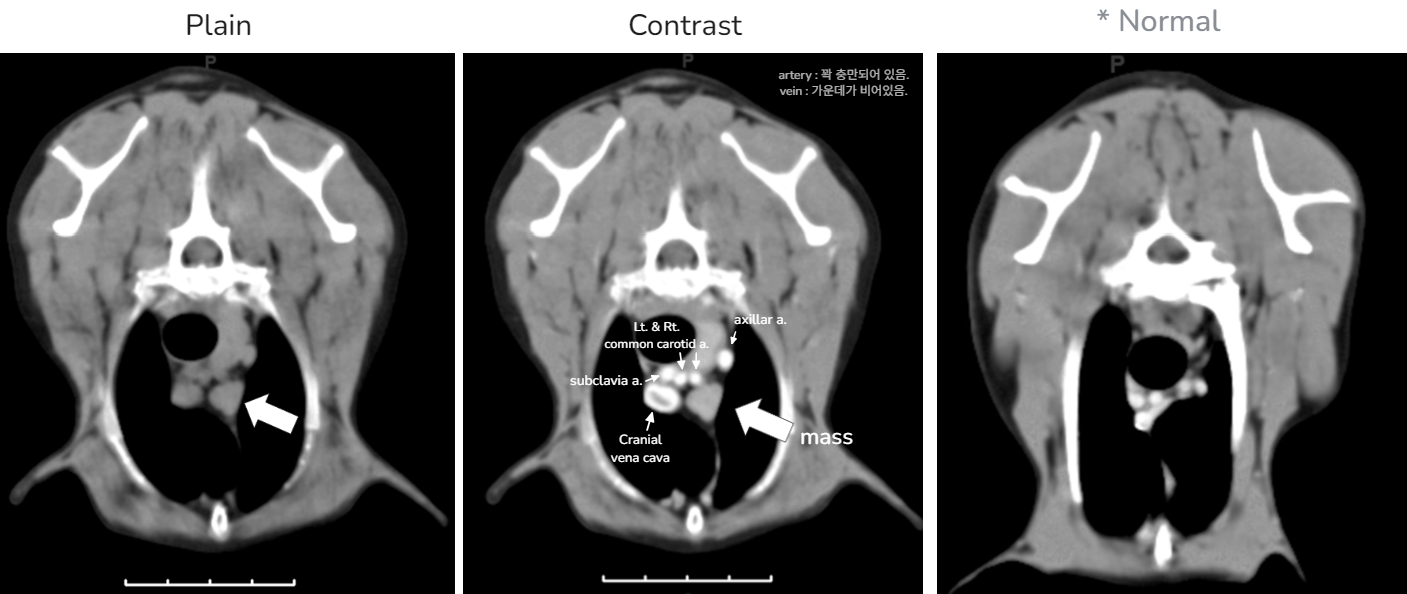

CT ์ดฌ์ - artery๋ ์์ง๋ง ์์ ๋น ๊ณต๊ฐ์ด ์์ด ํ์๋ค (ํ์ก ํ๋ฆ์ด ๋น ๋ฆ)

- vein์ ์ข ๋ ํฌ๊ณ ๊ฐ์ด๋ฐ๊ฐ ๋๋์ฒ๋ผ ๋น์ด ์๋ค (ํ์ก ํ๋ฆ์ด ๋๋ฆผ)

- ๊ทธ๋ฐ๋ฐ artery๋ vein๋ ์๋ ๋ฌด์ธ๊ฐ๊ฐ ์๋ค - ๋๊ฒ ์์์ X-ray์์๋ ๋์ค์ง ์์.โ CT์ ์์ thymoma๊ฐ ๊ด์ฐฐ๋จ.

โ ์์ ์ ์ผ๋ก ์ ๊ฑฐํ๋๋ ์ฝ๋ ํ์ ์์ด ์ฆ์์ด ์น ๋์.โ ์ต์ข ์ง๋จ : Thymoma์ ์ํ ์ค์ฆ ๊ทผ๋ฌด๋ ฅ์ฆ (์ฐ๋ฆฌ๋๋ผ ์ต์ด์ ์ผ์ด์ค) (๊ต๊ณผ์์์๋ thymoma = cranial mediastinum์ ํฐ ์ข ์์ด๋ผ๊ณ ๋์ด, ํ์ง๋ง ์ด๋ ๊ฒ ์์ small size thymoma๋ ์์ ์ ์๋ค. ๊ต๊ณผ์์๋ ์ ํ์ ์ธ ๊ฒ๋ง ์๋ค~!)